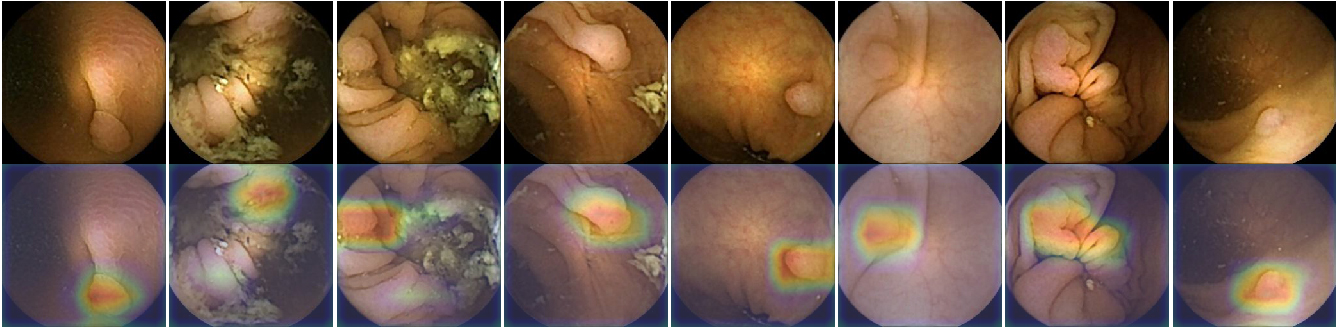

CAM visualization was applied to the output of the network. This method generates a heat map, where the red tones show the regions of the image that obtain a high response from the filters. Figure 9 shows in the first row eight polyps frames where the different morphology and size of the polyps may be observed. In the second row, the CAM visualization method highlights the location where the system focused to predict that there was a polyp.

Figure 10 shows eight images without polyps where the system has erroneously detected a polyp. In these samples, some of the regions highlighted by the network contain features of polyps such as growths of tissue, mucous membranes or areas with reddish colour from the wall, that might indicate the existence of it.